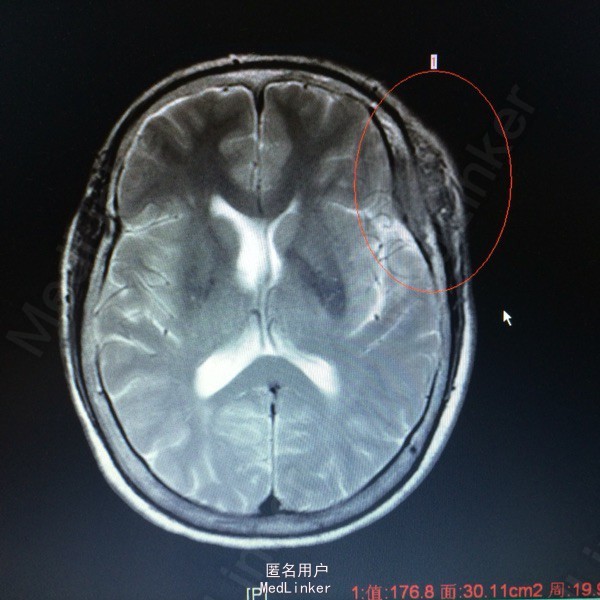

主诉:发现左侧额颞部包块2年余 病史:患者63岁女性,2年前无明显诱因出现左侧额颞部包块,无压痛等症状。1个月前开始出现左侧额颞部麻木不适,于外院查头颅MR提示:左侧额颞部占位。

查体:左侧额颞部可扪及一3*3大小隆起,无红肿,溃疡等。左侧眼球突出。 辅助检查,我院MR提示:左侧蝶骨大翼,额颞骨、中颅窝低,左眶顶璧、外侧璧骨质破坏,考虑恶性肿瘤的可能性较大。

诊断:左侧额叶非典型脑膜瘤 处理:行左额占位切除术➕颅骨重建术,病理提示非典型脑膜瘤